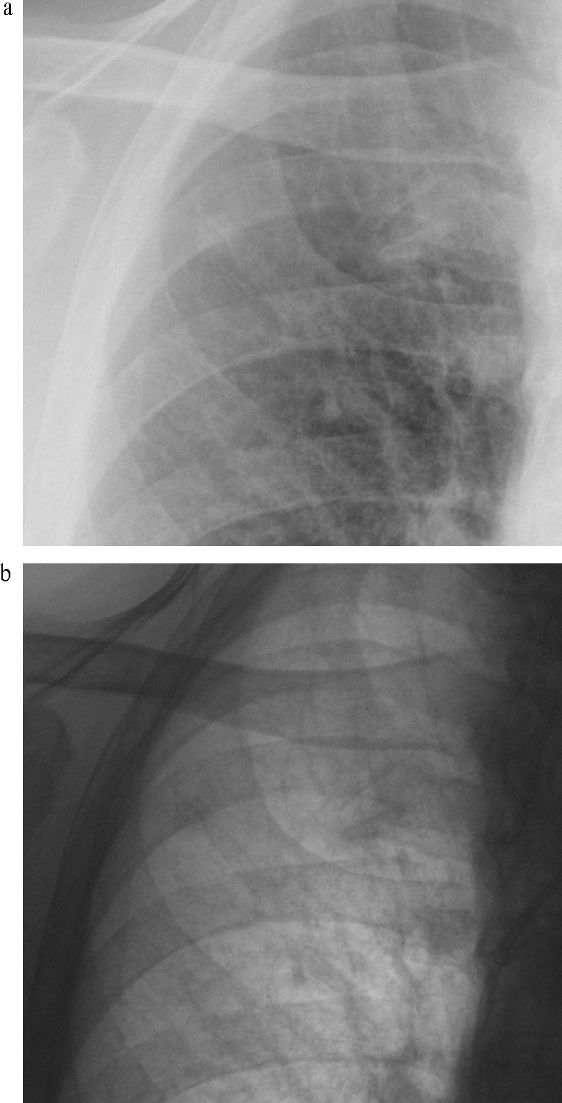

Chest radiographs and CT can identify unique features of the H7N9 virus which may assist in the proper initiation of treatment.